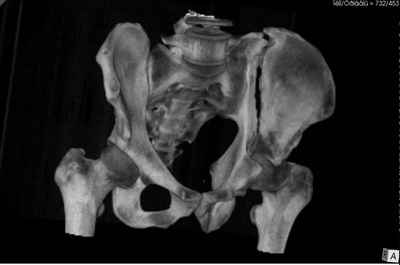

Добрый вечер уважаемые коллеги. Госпитализирован пациент с переломом таза 9-ти месячной давности (лечился где-то в районе консервативно). Помогите определиться с оптимальным вариантом хирургического доступа, фиксации.

Пациенту чуть больше сорока лет, работал в МЧС, после ДТП лечился по месту жительства консервативно. Жалобы пациента на постоянные боли в месте перелома, ощущение подвижности в месте перелома при ходьбе. Передвигается без дополнительной опоры, хромота не щадящая. Клинически отчетливо определяется патологическая подвижность крыла левой подвздошной кости. R-ммы не высылаю, сразу 3-D, если не хватит дошлю снимки.